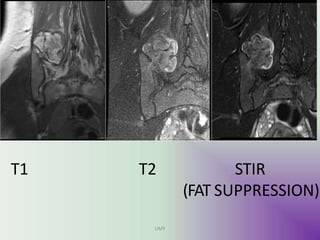

MRI

MRI is best at assessing

cartilage thickness (and thus

assessing for malignant

transformation), presence of

oedema in bone or adjacent

soft tissues and visualising

neurovascular structures in the

vicinity.

The cartilage cap of

osteochondromas appears the

same as cartilage elsewhere,

with intermediate to low signal

on T1 and high signal on T2 and

STIR weighted images.

A cartilage cap of over 1.5cm in

thickness is suspicious for

malignant degeneration.

UMY

T1 T2 STIR

(FAT SUPPRESSION)